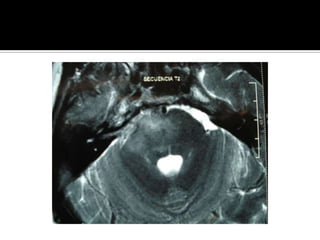

¿Pregunta 2?¿Cual es la localizacion y magnitud de la lesion?Respuesta: TAC o RM

¿Pregunta 2?¿Cual esla localizacion y magnitud de la lesion?Respuesta: TAC o RM